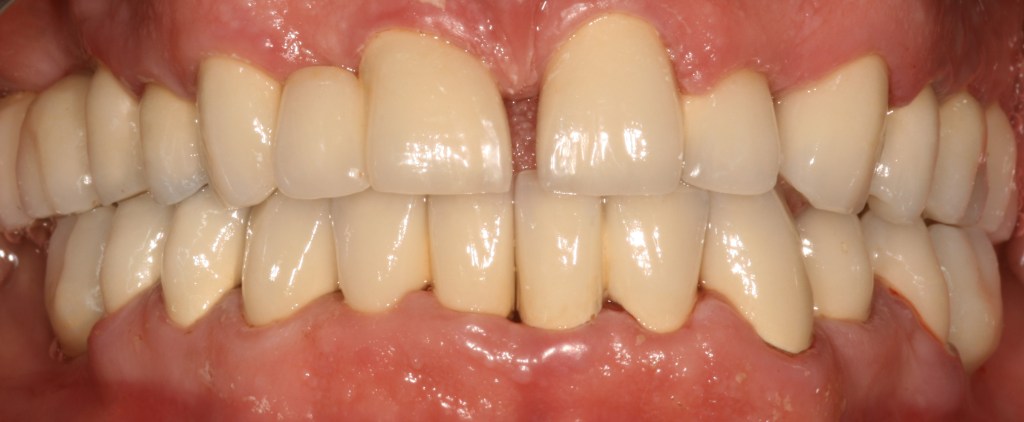

Kozmetikai és funkcionális kezelés: felső torlódott fogak kiegyenesítése, koronák enyhe kifele döntése, mélyharapás korrigálása.

A választott korona típusa: CAD/CAM (komputer vezérelt tervezés/megmunkálás) technológiával készült cirkónium (fémmentes) szóló koronák.

A választott fogszín: A2

A protetikai munka elkészülésének ideje: 5 munkanap.